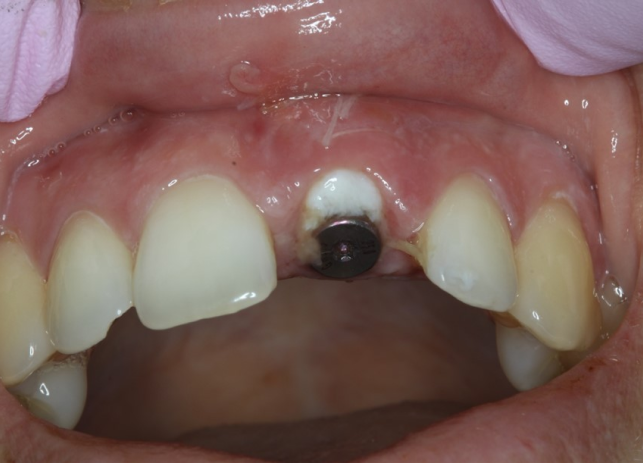

Клинический пример: пациент сломал левый центральный резец и решил удалить все четыре передних зуба и заменить их коронками с опорой на имплантаты.

Рис. 23 Итоговый результат лечения с установленным мостовидным протезом 12-22 на имплантатах. Обратите внимание на естественный профиль ткани после извлечения 12, 11, 21 и 21